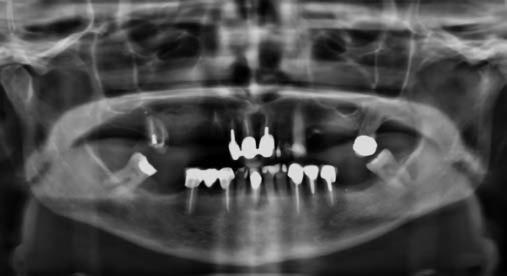

Egy fiatal páciens jelentkezett nálunk, akinek eltörött a szabad véggel rendelkező hídja (1. ábra). A hiányzó, első premoláris fog esetén implantációs pótlást javasoltunk. A csontállomány értékeléséhez CBCT-vizsgálatot végeztünk, és az elemzéséhez NNT Viewert (NewTom) használtunk, és copaSKY 4×10 mm-es (bredent medical) implantátumot választottuk a fog pótlásához

1. ábra: Műtét előtti fogászati panorámafelvétel, amelyen a hiányzó felső állcsont jobb első premolárisát és a szabad véggel rendelkező hidat láthatjuk. — 2. ábra: Az implantátum méreteinek megtervezése CBCT-vel. 3. ábra: Bukkális lágyrészdefektus. — 4. ábra: A biológiai szélesség értékelése a vertikális lágyszövetvastagság alapján. 5. ábra: Palatinális „tekercslebeny” – Palatal roll flap. — 6. ábra: Bredent medical copaSKY 4x10 implantátumbeültetés. 7. ábra: Szubkresztális implantátumbeültetés a várható biológiai szélességnek megfelelően.

(2. ábra). A lágyszövetek értékelése Seibert szerinti I. osztályú csontdefektust állapított meg (3. ábra), ezért a beavatkozáskor palatinális „tekercslebenyt” preparáltunk (palatal roll flap), és implantációt végeztünk, hogy kompenzálni tudjuk a bukkális lágyszövet-behúzódást. Megmértük a vertikális lágyszövetvastagságot, és úgy terveztük, hogy a szubkresztális implantátum beültetése összhangban legyen a biológiai szélesség kialakulásával a transzgingivális gyógyulási periódus alatt (4. ábra)